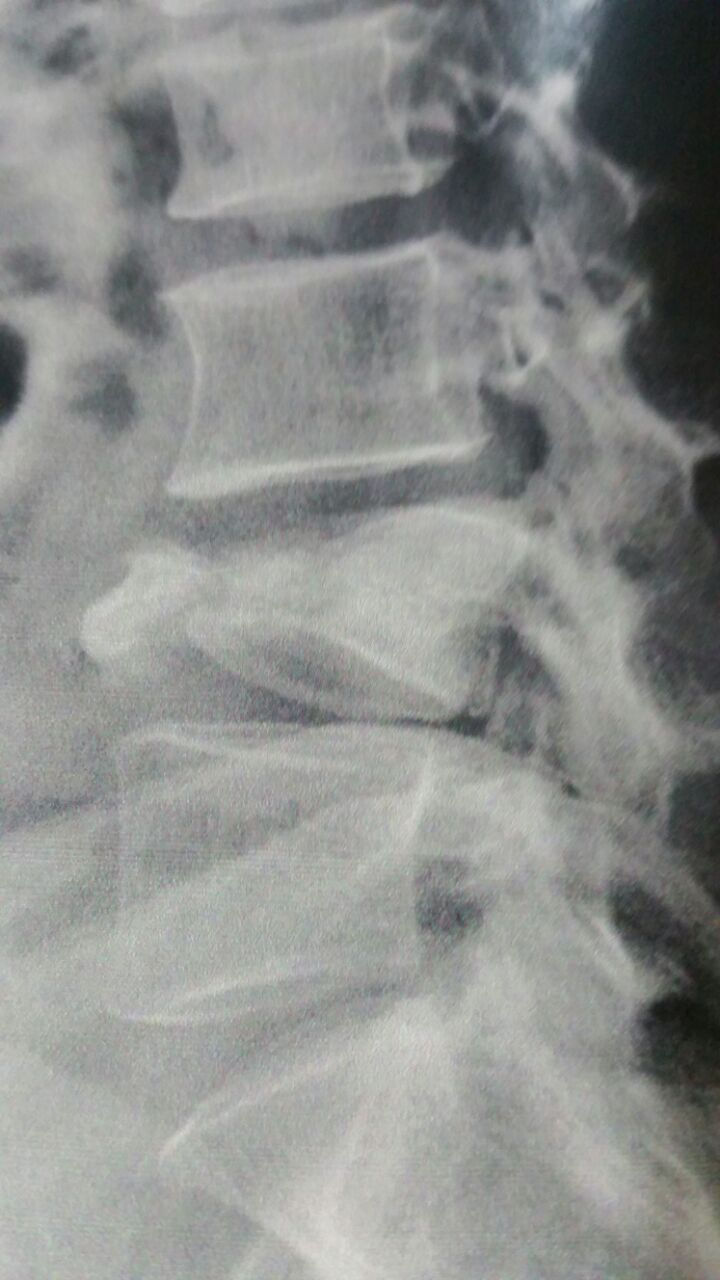

Imagem radiológica de fratura de vértebra lombar.